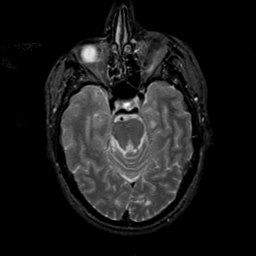

MR Study #21, November 3, 1991 -- Slice #17